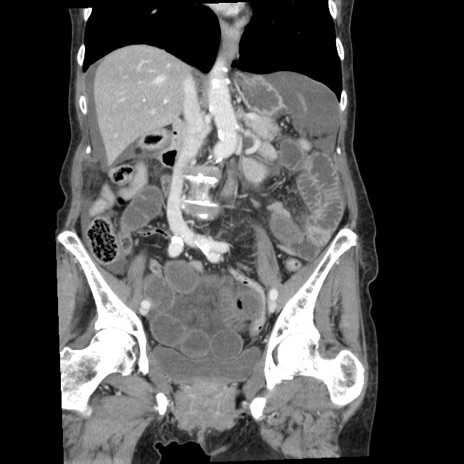

症例1(冠状断像)

【症例】80歳代女性

【主訴】腹痛

【現病歴】8時間前から腹痛あり来院。

【既往歴】糖尿病、脂質異常症、子宮体癌にて子宮全摘術

【身体所見】意識清明・会話良好だが腹痛で苦悶様、全腹部にわたって反跳痛と圧痛あり

【データ】WBC 13600、CRP 0.14、LDH 224、CK 90